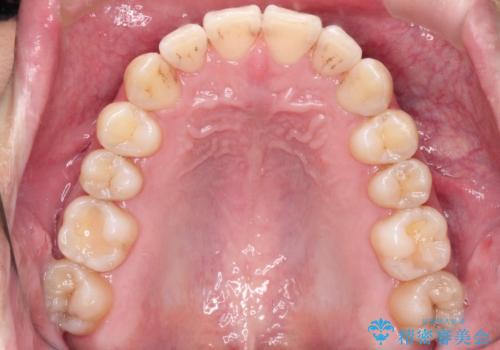

- 前歯の凸凹を主訴に来院された患者様です。

インビザラインにて治療を行いました。

- 1年6ヶ月